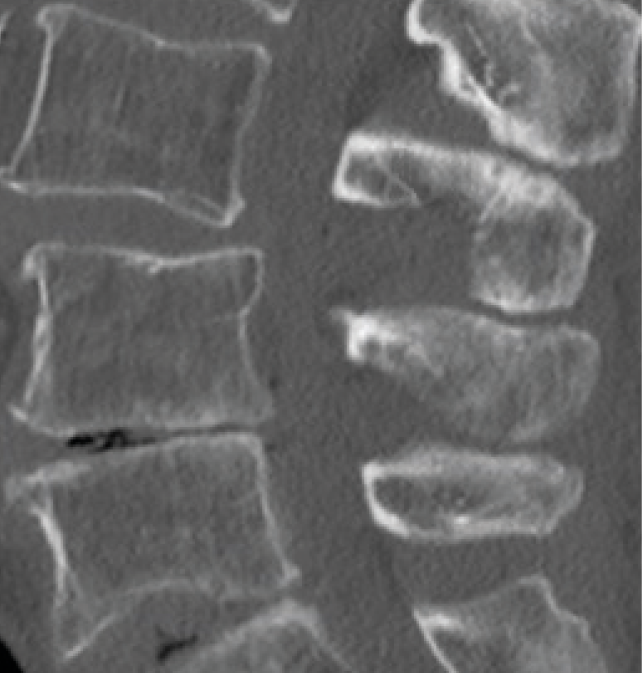

Decompression of lumbar spinal stenosis in medialized cross-over technique (mCOT):

Exposure of the spinolaminar connection. Removal of bone tissue from the deeper half

Decompression of the contralateral dural sac and root.

Decompression of access side.